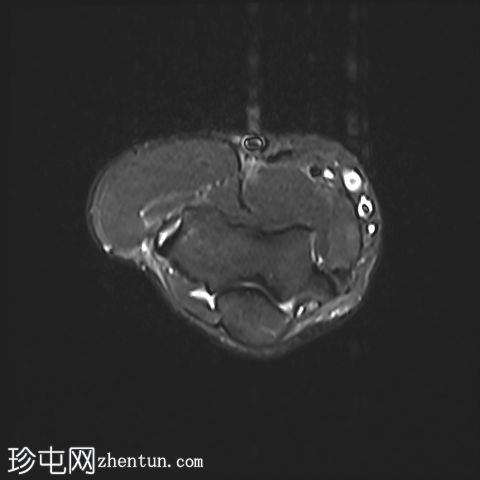

轴位

T2加权像

STIR序列

肘关节伸肌总腱增厚,腱内可见高信号及部分撕裂。伴周围软组织水肿。